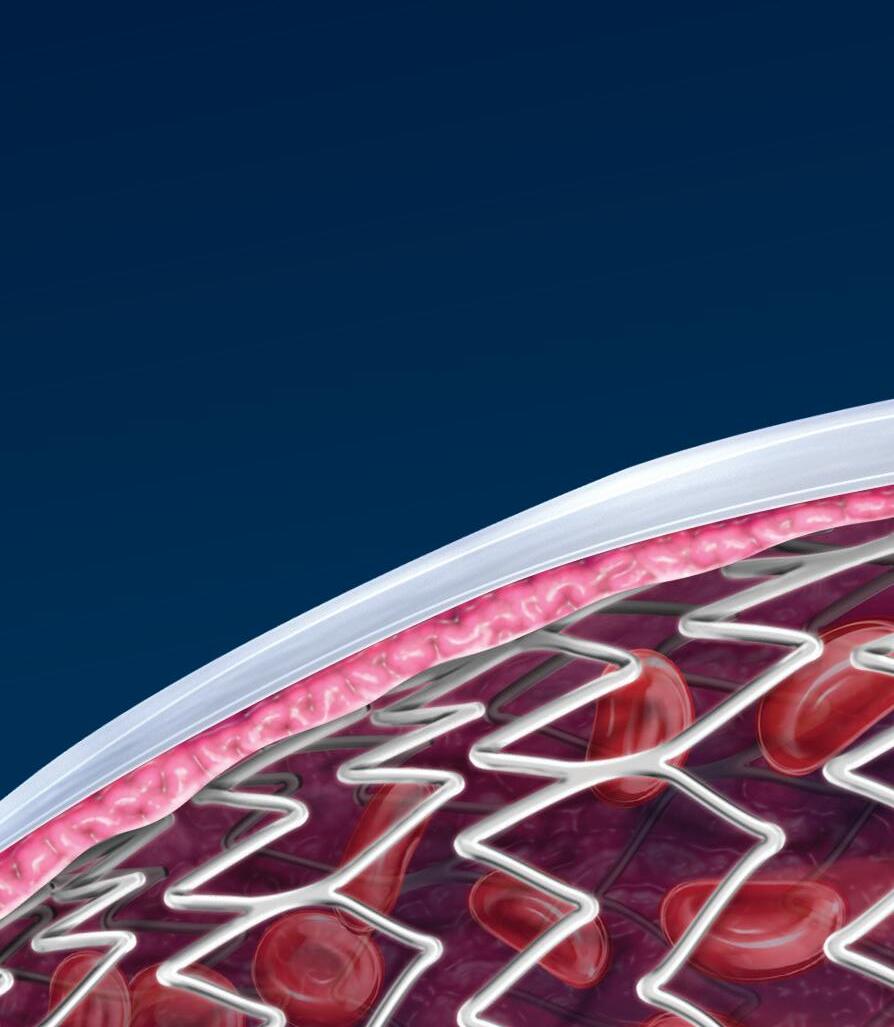

The REALITY Study, sponsored by the VIVA physicians,1 demonstrates how the use of the HawkOne™ directional atherectomy system, followed by the IN.PACT™ Admiral™ drug-coated balloon (DCB), can help achieve positive patient outcomes in treating peripheral artery disease.

Outcomes in complex, long, heavily calcified lesions2: Bailout stent rate

92.6% 8.8% 12-month freedom from CD-TLR†

HawkOne Directional Atherectomy System

IN.PACT Admiral Drug-Coated Balloon